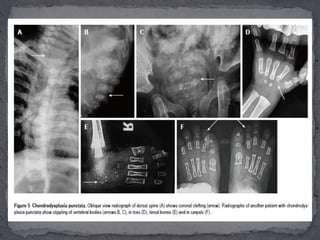

 Chondrodysplasia punctata (CDP) is another

genetically heterogeneous dysplasia. The most

common type is the X-linked dominant type also

termed as Conradi-Hunermann type due to mutation

on Xp11. Another type is the rhizomelic type

chondrodysplasia punctata (RCDP) associated with

peroxisomal enzyme disorder and has an autosomal

recessive inheritance.

 RCDP is further divided into 3 sub-types, namely

RCDP1,RCDP2 and RCDP3.

 Essentially, the hallmark of CDP is stippling of

epiphyses at birth. Later on, the stippling disappears

and epiphyses become irregular with limb asymmetry.